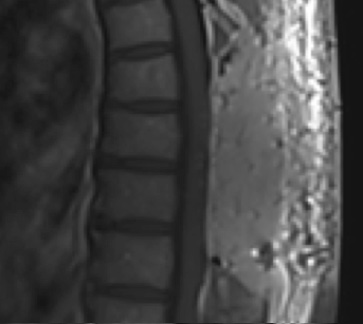

This is a 55-year-old female with no past medical history who presented electively with a 10 month history of progressively worsening mid back pain radiating across the chest, and gait disturbance. Pain was especially worse at night and when laying flat. Her exam was pertinent for severe ataxia when ambulating, and elevated deep tendon reflexes in the lower extremities. She had severe and debilitating symptoms, as demonstrated by her Visual Analog Scale (VAS) and Oswestry Disability Index (ODI) of 9/10 and 64/100, respectively. MRI of the thoracic spine with and without contrast demonstrated a large intradural extramedullary homogenously enhancing mass at T8, resulting in near obliteration of the spinal canal and severe cord compression. She was referred to Dr. Xavier Gaudin for neurosurgical management.